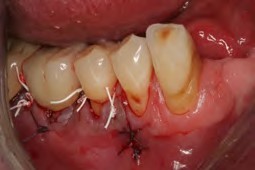

Recently, the literature has cited an approach for successfully managing peri-implantitis that combines mechanical and chemical methods for decontamination that encompasses eight specific steps.36,40,41 These steps include: critically evaluated case selection (Figure 15 through Figure 17); one-flap access (Figure 18); surface decontamination; defect debridement; placement of a biologic on the cleaned implant surface; filling defect with mineralized freeze-dried bone and/or using anorganic bovine bone (Figure 19); coverage with an absorbable membrane or subepithelial connective tissue graft (Figure 20); and coronal positioning of the flap (Figure 21). A subsequent requisite step is professional maintenance (Figure 22).40,41

Fig 18. The patient accepted treatment, and a flap was made. Surface decontamination was achieved without endangering the inferior alveolar nerve.

Figure 18